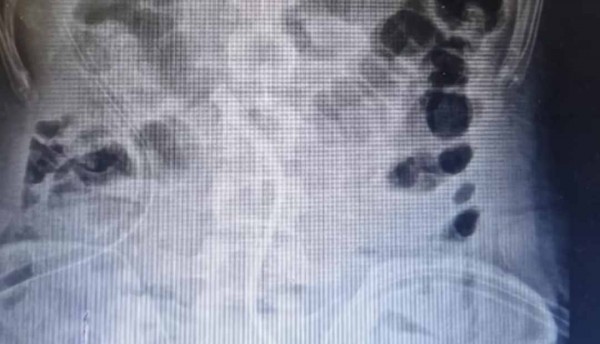

Hombre muere por sobredosis de vitamina D

David Mitchenner, un hombre de 89 años murió en Inglaterra por una sobredosis de vitamina D. David habría tomado esta vitamina en altas cantidades durante 9 …